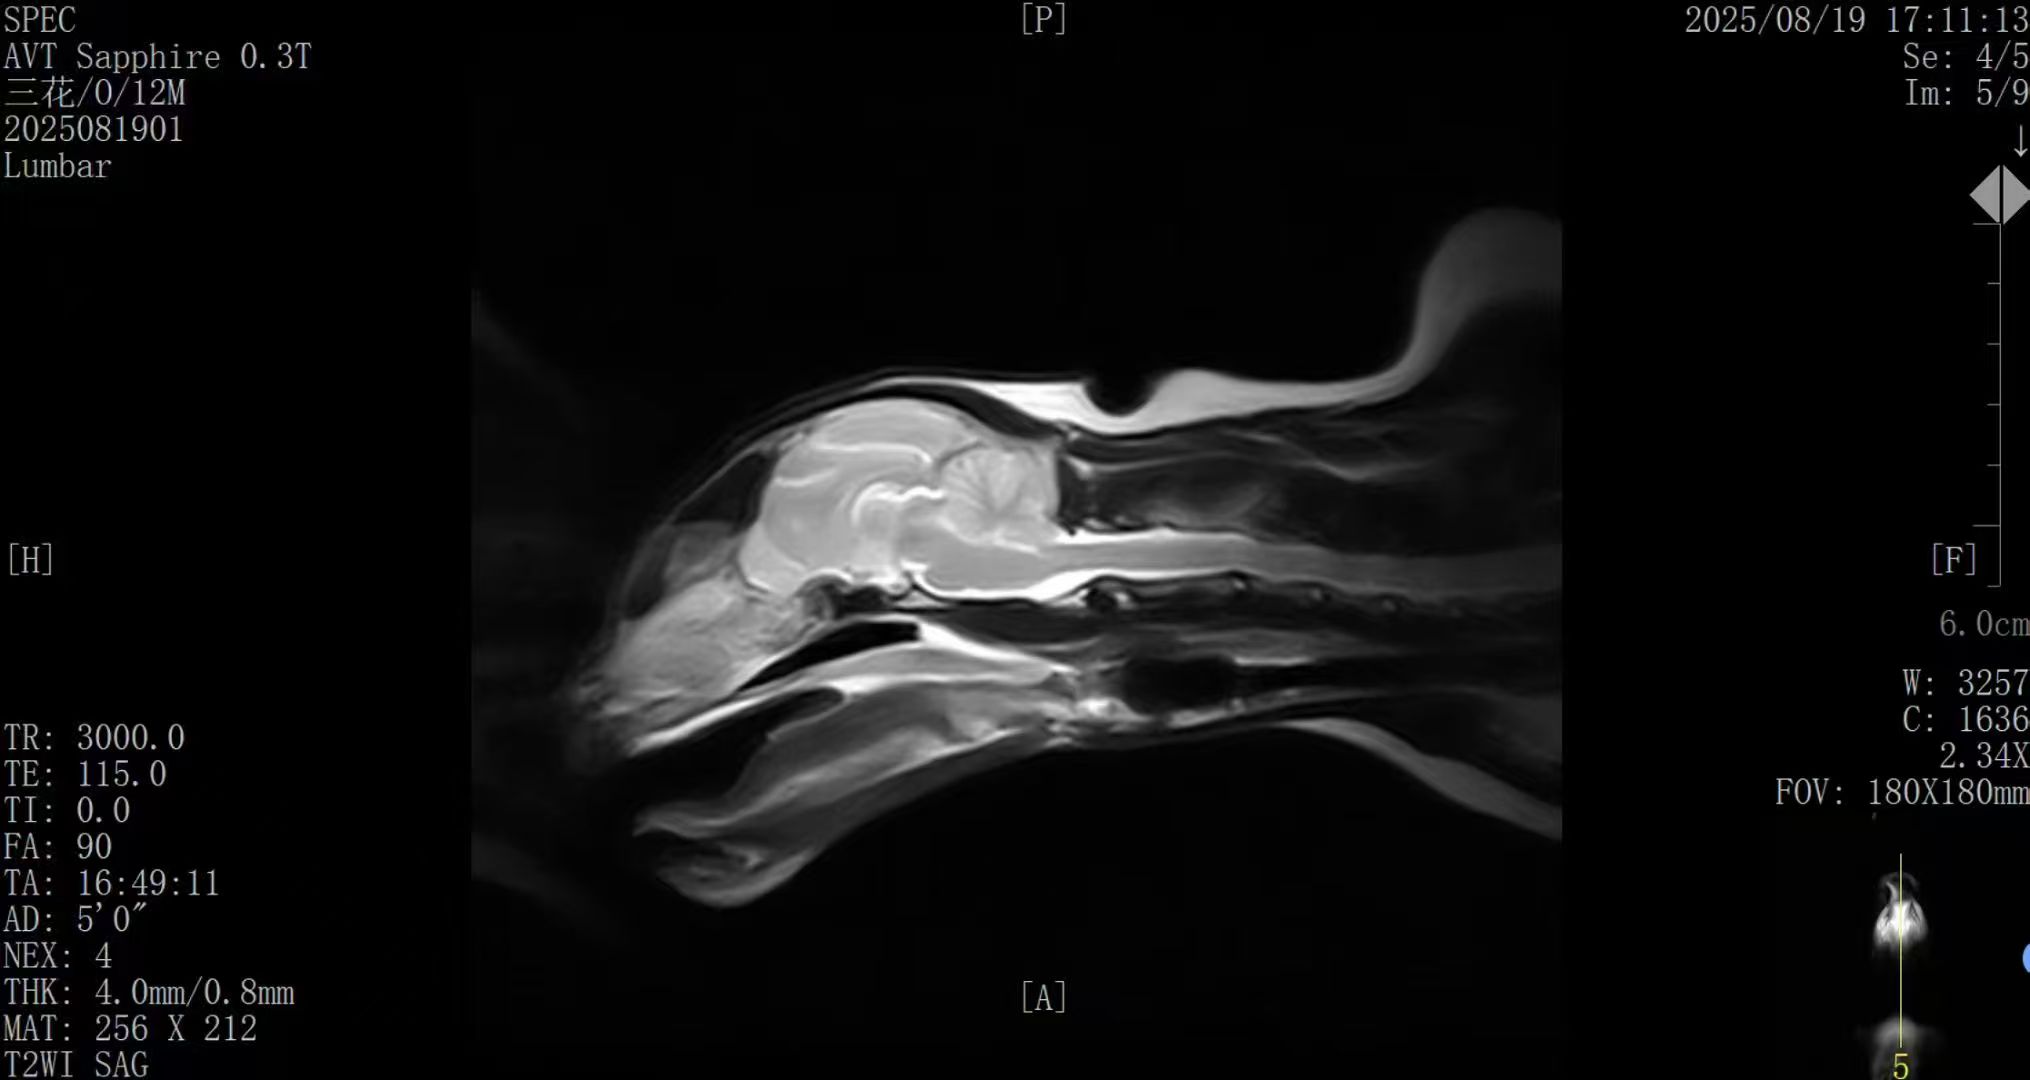

搭载新一代AI智能影像增强降噪系统,通过智能算法优化成像信噪比与组织对比度,整体图像质量提升约50%;

在神经、脊柱、关节、软组织等专科影像中表现出色,为临床诊断与治疗规划提供清晰可靠的图像依据;

图像质量已在国内多家合作医院中获得验证,能够满足从基础诊断到专科评估的多层次需求。